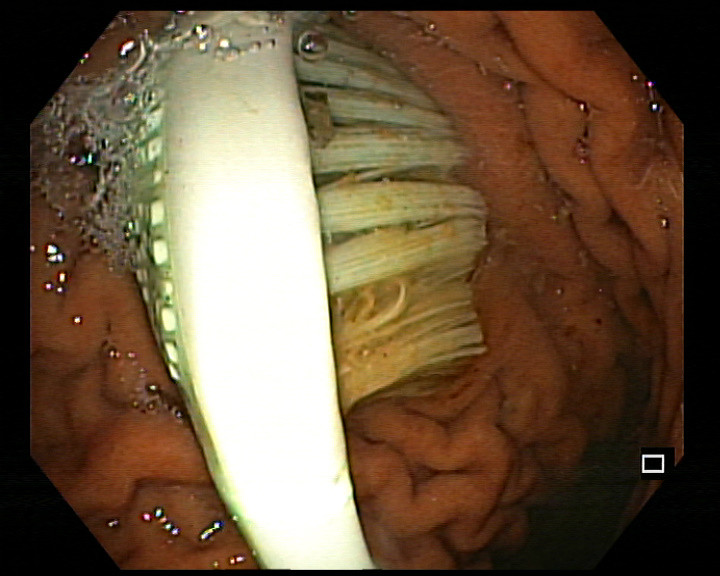

| Hình ảnh bàn chải qua thiết bị nội soi nằm trong dạ dày. Ảnh do Bệnh viện đa khoa tỉnh Thanh Hoá cung cấp. |

Do dị vật lớn, cứng, dài (khoảng 20cm) nên khi thực hiện thủ thuật nội soi, bác sĩ phải cẩn thận, tỉ mỉ để tránh nguy cơ làm tổn thương dạ dày, thực quản của bệnh nhân. Sau thủ thuật, hệ hô hấp, tuần hoàn ổn định, bệnh nhân cảm thấy thoải mái, hết đau bụng, ăn uống bình thường.